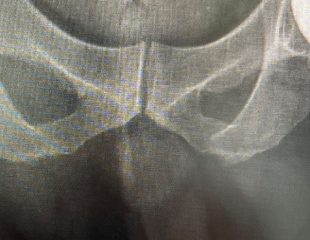

Dấu hiệu của đứt dây chằng chéo trước và đứt dây chằng chéo sau Thứ Năm, 30/10/2025

Tìm hiểu các dấu hiệu của đứt dây chằng, cách phân biệt dây chằng chéo trước và dây chằng chéo sau, cùng phương pháp chẩn đoán chính xác.